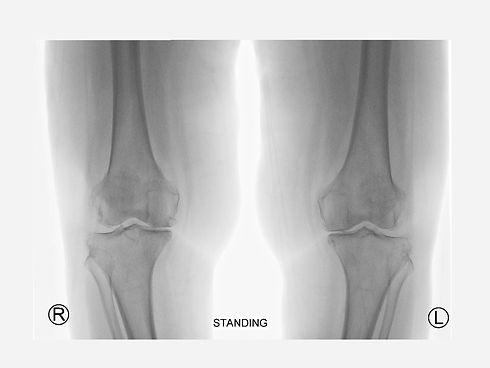

Είμαι υποψήφιος ασθενής για αρθροπλαστική γόνατος;

Μπορεί να είστε υποψήφιος για ολική αρθροπλαστική γόνατος εάν έχετε οστεοαρθρίτιδα με πόνο που δεν έχει ανταποκριθεί επαρκώς σε πιο συντηρητικές μεθόδους θεραπείας, όπως φυσικοθεραπεία, φάρμακα και ενδαρθρικές ενέσεις. Αν και οι αρθροπλαστικές γόνατος θεωρούνται ασφαλείς και εξαιρετικά επιτυχημένες ως επεμβάσεις, τα αποτελέσματα εξακολουθούν να διαφέρουν από ασθενή σε ασθενή. Είναι σημαντικό να συζητήσετε τις επιλογές σας με τον ορθοπεδικό σας για να προσδιορίσετε εάν η ολική αντικατάσταση γόνατος είναι κατάλληλη για εσάς.